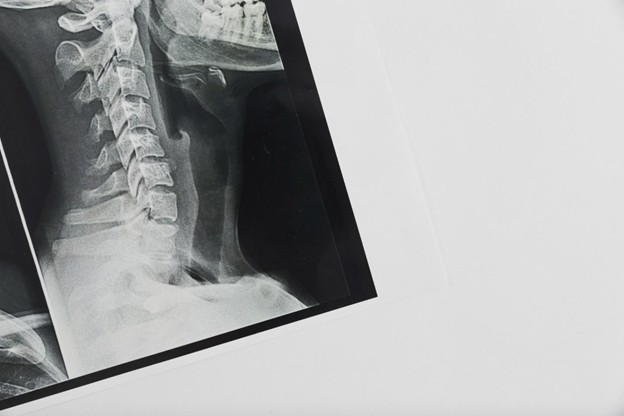

Рентгенография шейного отдела позвоночника — один из базовых методов лучевой диагностики, позволяющий визуализировать костные структуры в области шеи. У детей исследование проводится строго по показаниям, с применением современных аппаратов, обеспечивающих минимальную лучевую нагрузку при высокой диагностической точности.

Процедура проводится в специализированном рентгенологическом кабинете. Используются аппараты, оснащенные цифровыми матрицами, что позволяет получить изображение высокого разрешения с минимальной дозой излучения.

Продолжительность исследования составляет в среднем 5–10 минут. Лучевая нагрузка соответствует международным рекомендациям и является безопасной для ребенка. При необходимости проводится повторная съемка для получения четкого изображения.

Результаты рентгенографии оценивает врач-рентгенолог. В заключении отражаются все выявленные изменения с указанием их анатомической локализации, степени выраженности и клинической значимости. Снимки сохраняются в цифровом формате и могут быть переданы лечащему врачу или предоставлены родителям по запросу.